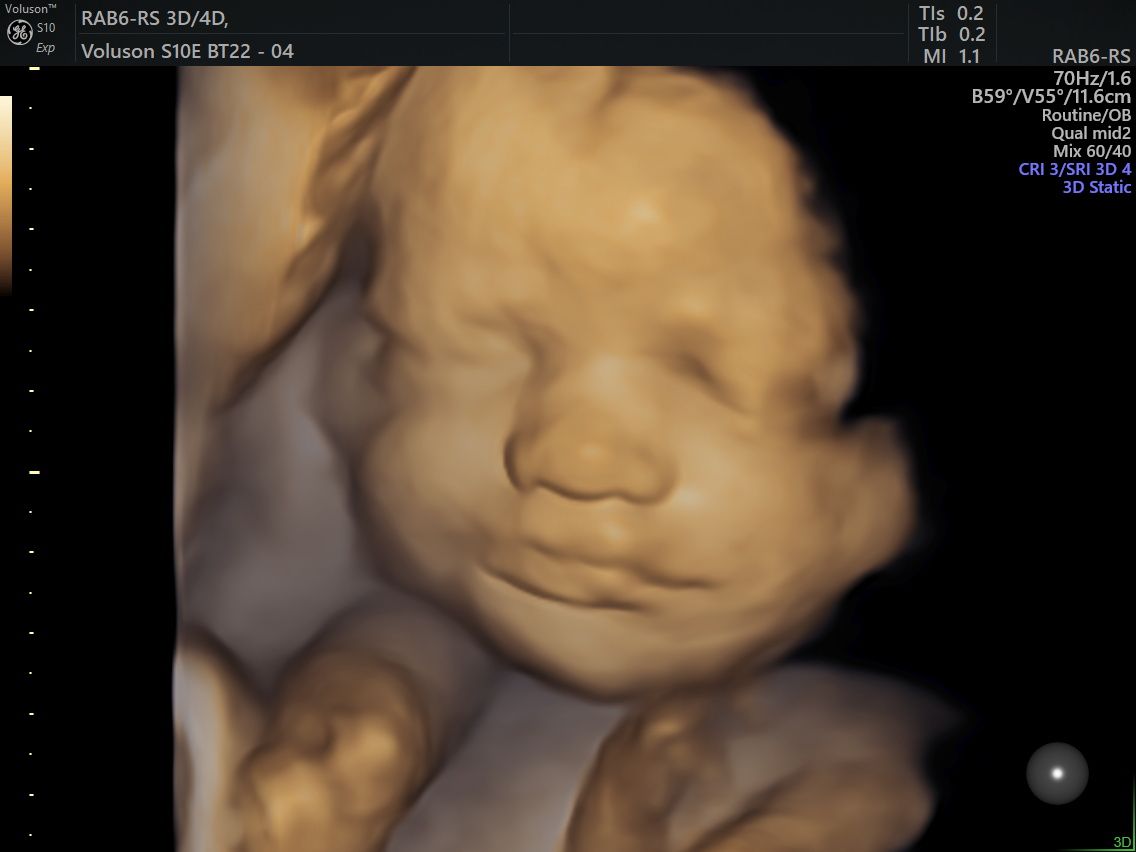

Durante gli studi in medicina sento che la mia vocazione è la ginecologia, un’affascinante specialità tutta incentrata sulla donna che mi ha permesso di studiare la patologia ginecologica e oncologica (in particolare di perfezionarmi come ultraspecialista in diagnostica ecografica ginecologica ed ostetrica di 2 livello).

Ho raffinato negli anni di studio le mie conoscenze per poter fare diagnosi complesse in ambito sia ginecologico che ostetrico dove ho perseguito il sogno di far nascere i bambini e ancor prima di poterli guardare in pancia e aiutare le donne nel loro percorso per la vita a diventare madri…

Foto e video